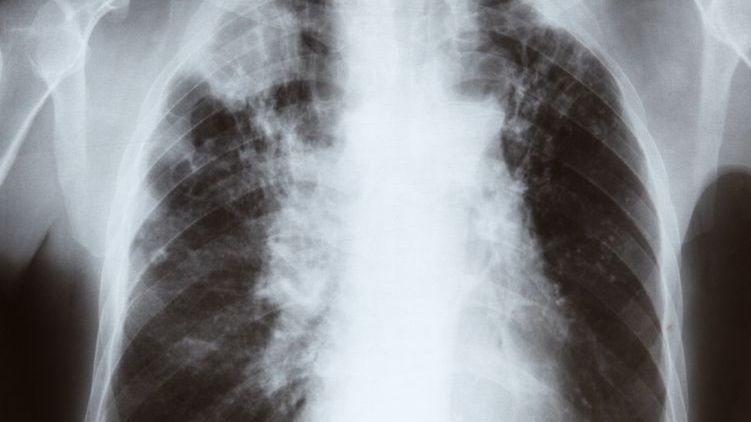

POChP to przewleła choroba. Trzecia przyczyna zgonów.POChP to przewleła choroba. Trzecia przyczyna zgonów.

Źródło zdjęć: © 123RF

Szacuje się, że na POChP (przewlekłą obturacyjną chorobę płuc) cierpi 2 mln Polaków. Zdiagnozowanych jest jedynie ok. 600 tys. chorych. POChP to trzecia najczęstsza przyczyna zgonów w naszym kraju. Nieleczona skraca życie nawet o 15 lat. Zbyt późno wykryta prowadzi do inwalidztwa.

- To złożone, niejednolite schorzenie. Obejmuje przewlekłe zapalenie oskrzeli i rozedmę płuc. Dochodzi wtedy do uszkodzenia miąższu płuc. Spada wydolność oddechowa - tłumaczy serwisowi WP abcZdrowie dr Piotr Dąbrowiecki, alergolog i internista z Wojskowego Instytutu Medycznego, przewodniczący Polskiej Federacji Stowarzyszeń Chorych na Astmę, Alergię i POChP.

- U zdrowego człowieka powierzchnia płuc zajmuje od 80 do 100 metrów kwadratowych, u chorego z ciężką postacią POChP jedynie 20-30 metrów - tłumaczy lekarz.